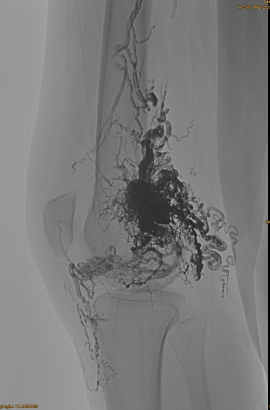

DSA tosaigh:

Toradh deiridh:

Is beag aon eis -sreabhadh venous:

Céim déanach, EMBO eile riachtanach, ach i bhfad níos fearr: